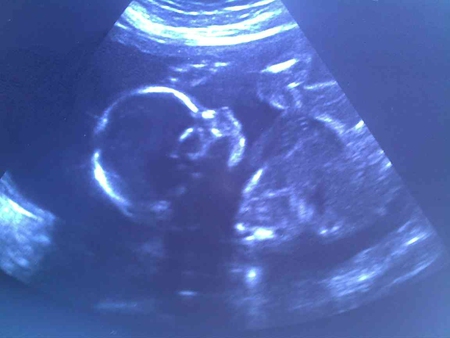

Последний 3-ий скриннинг:)

Ну вот мы и прошли последнее УЗИ с допплерометрией!

Ну что хочется сказать) МЫ ЗДОРОВЕНЬКИЕ!!! Мы девочки)) ничего у нас не выросло) поэтому все интернет таблички и тесты оказались на 100% верны, когда предсказывали девочку))

Развиваемся мы хорошо) по плоду нам 33 недели и 2 дня) что на 6 дней меньше менструального срока:) воть так)

Весим мы 2 200 гр

всё в норме))

Допплерометрия меня порадовала)) никакой фетоплацентарной недостаточности у нас нет

Воды в норме, степень зрелости плаценты - 2, толщина - 24 мм.

Шейка матки - 3,5 см.

И внимание.... ЛЕЖИМ ГОЛОВКОЙ ВНИЗ

перевернулась наша девочка!!!! Лежит в головном предлежании, задний вид, позиция №2!